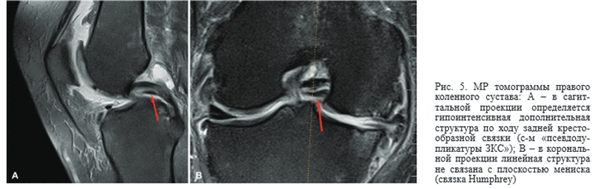

В редких случаях гипертрофированная связка Humphrey в сагиттальной плоскости имитирует смещенный лоскут мениска по типу «ручки лейки», определяясь в виде дупликатуры задней крестообразной связки, однако при совмещении с фронтальной плоскостью подозрительная структура интактна относительно плоскости мениска (в журнале «Skeletal radiology» такое состояние описано в виде симптома «Pseudo- double PCL sign» [10, 17, 18, 19] (рис. 5).